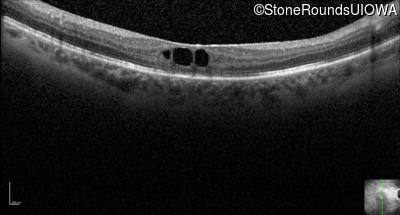

Optical Coherence Tomography - Left - 20/160

Exemplar / OCT Stack